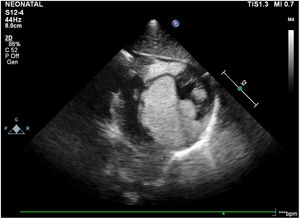

The mean age of postnatal diagnosis of patients was 82 days (3 days–10 months). The reasons for admission were a history of prenatally detected cardiac mass in 4 patients, seizures and hypopigmented lesions in 1 patient, murmur heard during neonatal intensive care monitoring due to meconium aspiration syndrome in 1 patient, premature delivery in 2 patients, and murmur heard on routine examination in 2 patients. 5 of 6 postnatally detected rhabdomyoma patients showed no clinical symptoms suggesting cardiac mass presence and 1 patient with a diagnosis of fetal cardiac rhabdomyoma had SVT. Multiple tumors were observed in the 9 patients (90%). The tumors were mostly located on the ventricular wall. The mean tumor diameter was 14.5mm (5–28mm). ECG abnormalities were detected in 5 patients. One of these patients (case 6) had SVT episodes during the neonatal period. After controlling SVT with adenosine, maintenance treatment with oral propranolol at a dose of 1mg/kg/day was initiated. One patient's ECG pattern (case 10) was considered to be compatible with Wolff–Parkinson–White syndrome because of the delta wave, PR interval of 70ms, and QRS duration of 140ms on the ECG. Hemodynamically insignificant incomplete right bundle branch block, supraventricular and ventricular premature beats were present in the other 3 patients. The mean follow-up period was 30.5 months (3–94 months). Hemodynamic obstruction developed in two patients (cases 6 and 8) during the follow-up period. In case 6 who had hemodynamically important left ventricular outflow tract (LVOT) obstruction (with the LVOT mean gradient of 45mmHg), prostaglandin E1 (PGE1) infusion was initiated (Fig. 1). Since rapid deterioration was observed in the patient's hemodynamic situation, the patient was referred for surgery. Pediculated mass in the left ventricular outflow tract was excised by approach through the aorta, and then the patient was followed in the intensive care unit with inotropic support in the postoperative period. Ventricular tachycardia (VT) and SVT attacks of the patient were controlled with cardioversion and amiodarone infusion. He stabilized from the postoperative 3rd day, but again on the postoperative 8th day his general condition was deteriorated and cardiac arrest occurred. Although he was resuscitated and the necessary supportive treatments were given, his blood pressure had remained low and he died on the 10th postoperative day. Case 8 was evaluated because of murmur heard 3-days postnatally. Echocardiography revealed a total of six tumors with diameters ranging from 3mm to 26mm in both the right and left ventricles, causing right ventricular outflow tract (RVOT) obstruction (RVOT gradient of 55mmHg) (Fig. 2). PGE1 infusion was initiated due to further increase in RVOT gradient. The patient also had isolated monomorphic ventricular premature beats that did not require treatment. After a week, PGE1 infusion was discontinued. Since the patient had extensive intramural tumor invasion and no signs of heart failure, surgical treatment was not considered. The patient was started on everolimus with a dose of 0.25mg at 12-h intervals, two days per week. Dose adjustments were made to maintain the serum level of everolimus between 5 and 15ng/mL. No adverse effects of the drug (transaminase elevation, hypertriglyceridemia, lymphopenia, fever, diarrhea, stomatitis, sinus infections, etc.) were observed during the follow-up period. The Patient was followed-up with 1 week intervals during patient's stay in the intensive care unit. Check-ups were made regularly every month until the age of 1 year. Everolimus treatment continued until the age of 1 year. The drug was discontinued when the 17mm tumor obstructing the RVOT regressed to 10mm and, the RVOT gradient reduced to 5mmHg following treatment. Three of the 6 tumors disappeared while the others showed partial regression (left ventricle tumor regressed from 16mm to 13mm, right ventricle tumor from 26mm to 16mm, and RVOT tumor from 17mm to 10mm). Follow-up was continued at 6-month intervals after the drug was discontinued. No increase in tumor size was detected in the follow-ups.

Transthoracic echocardiography demonstrated multiple rhabdomyomas with diameters of up to 16mm (shown with arrows) in the left ventricular apex, IVS (A), and in LVOT which almost completely obstruct the aortic valve (B), in case 6. RV: right ventricle; LV: left ventricle; LA: left atrium; IVS: interventricular septum; Ao: aorta.